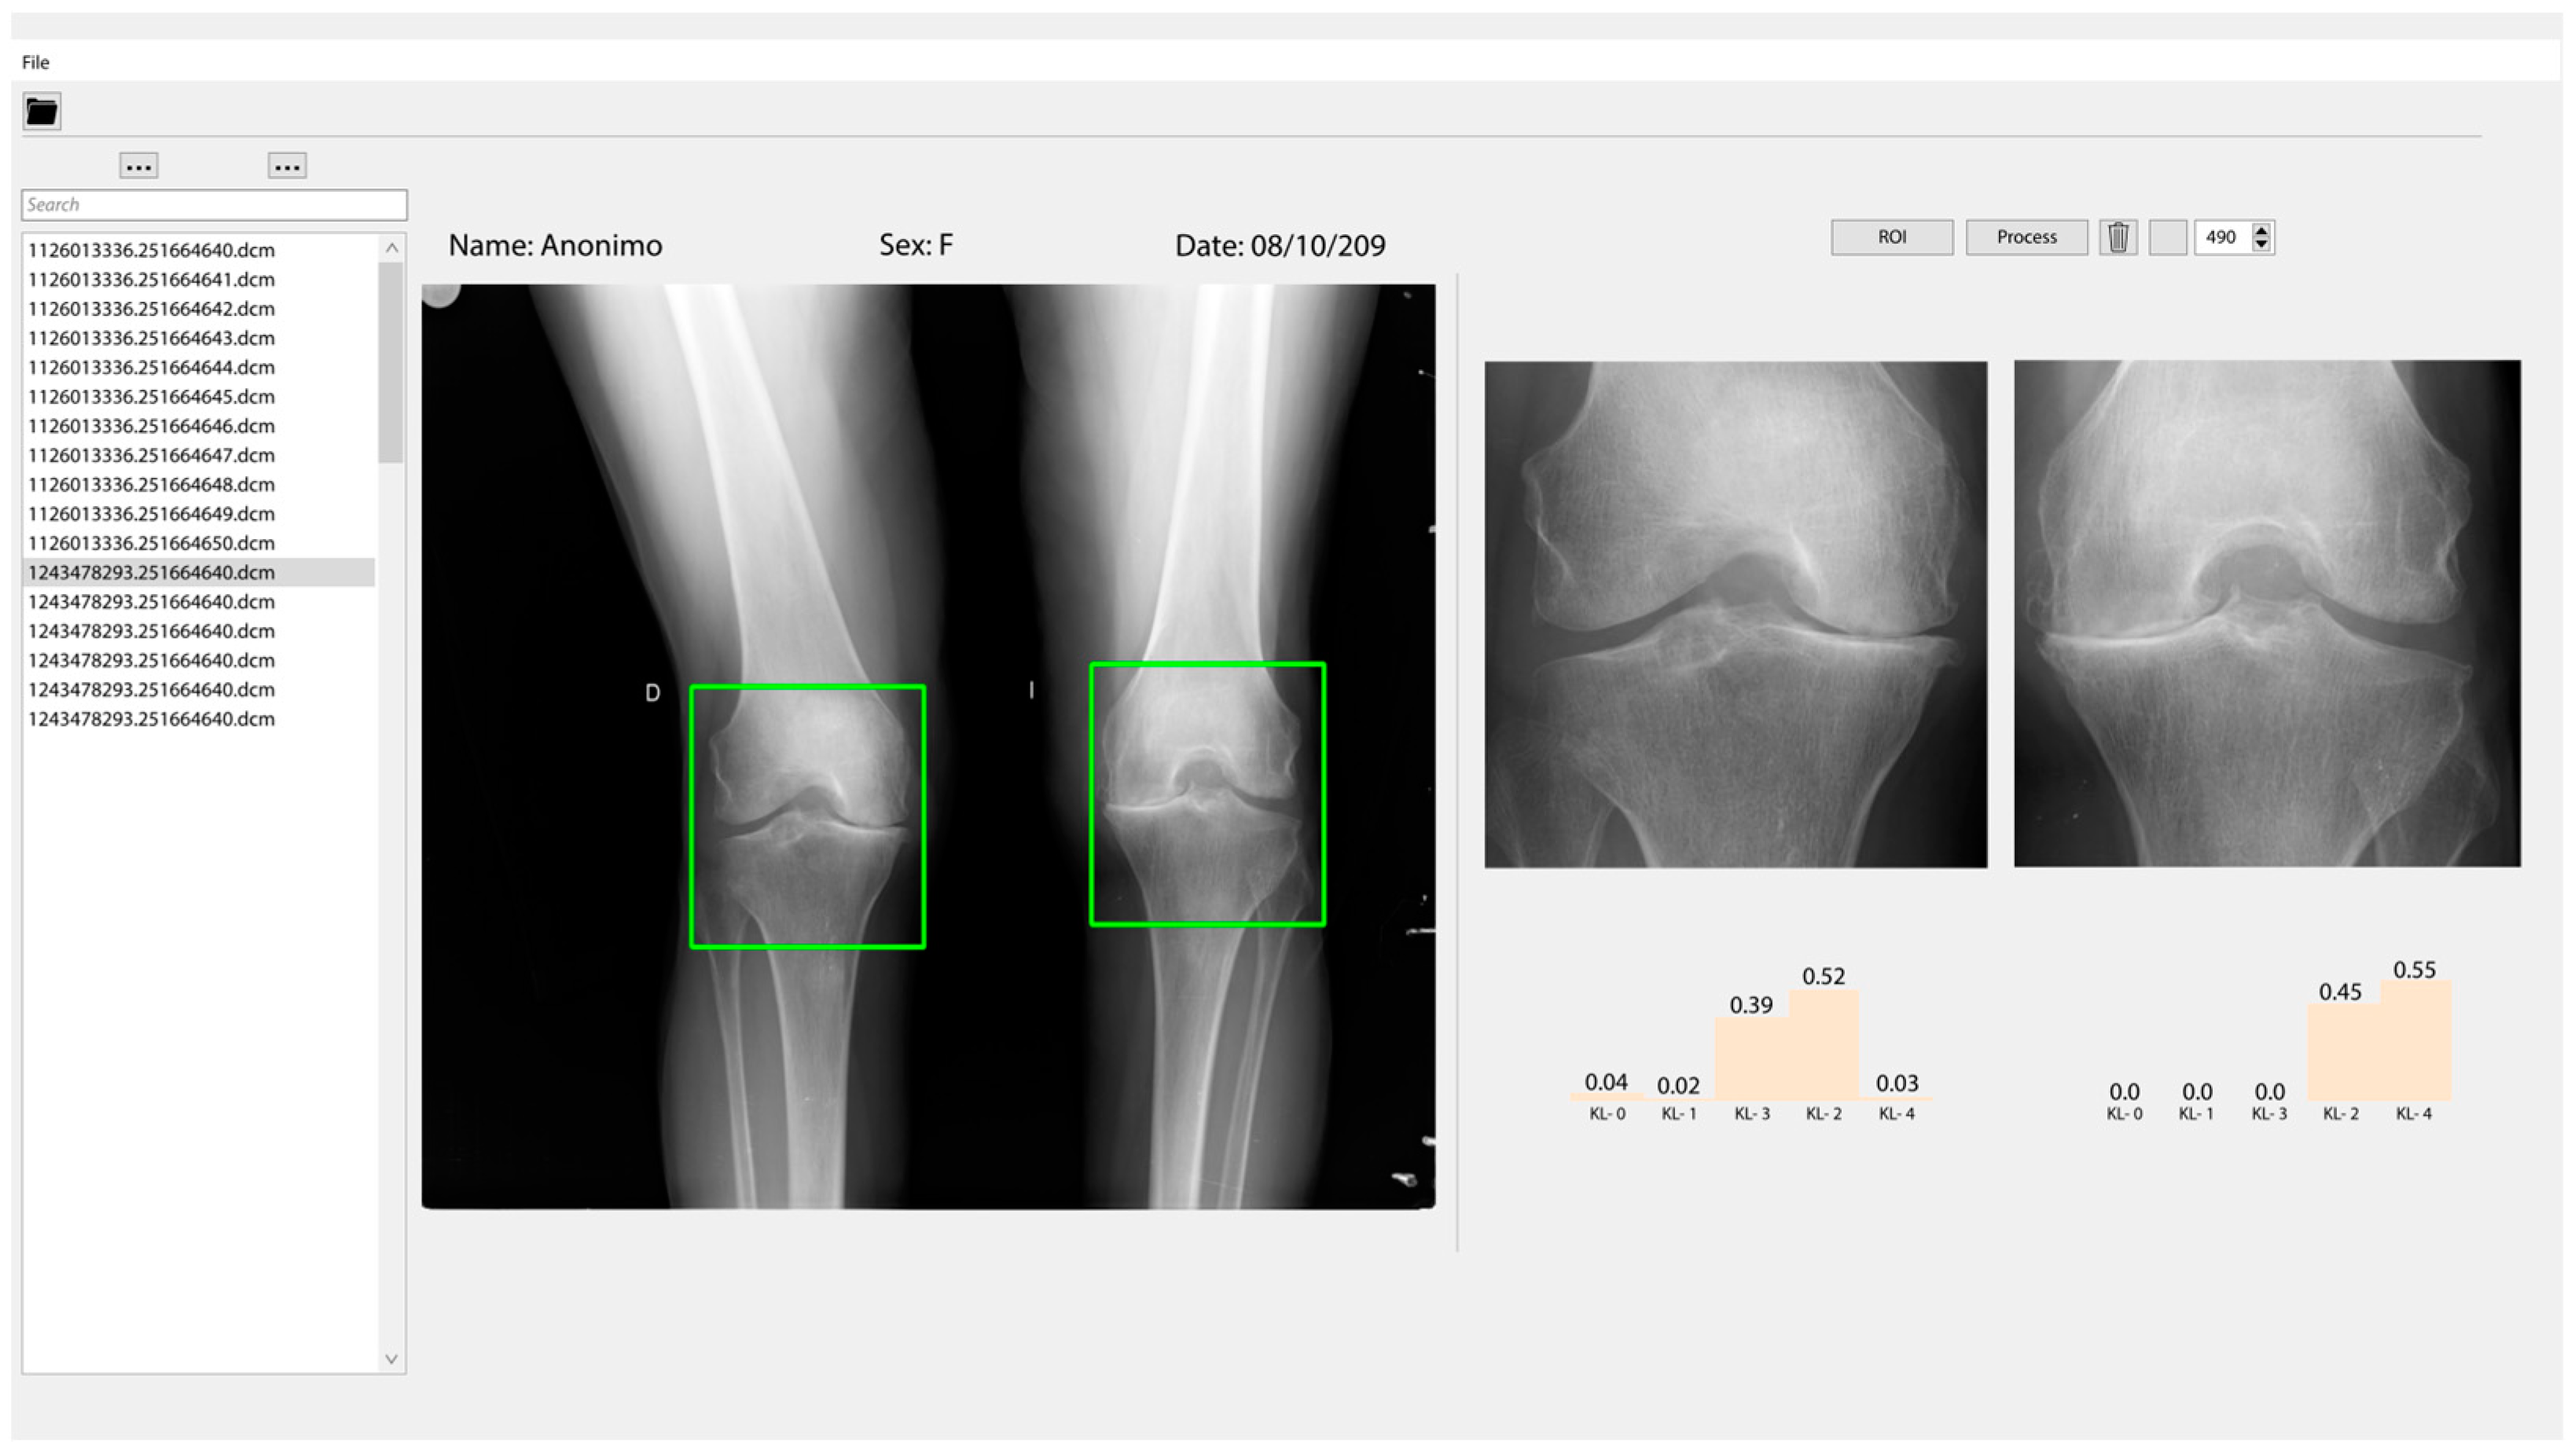

3.3. Classification and User Interface